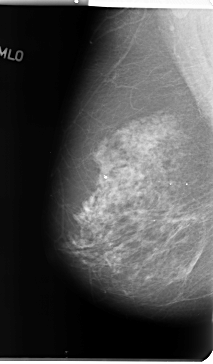

B_3131_1.RIGHT_MLO

LEFT_MLO LINES 4672 PIXELS_PER_LINE 2768 BITS_PER_PIXEL 12 RESOLUTION 50 OVERLAY

FILE: B_3131_1.LEFT_MLO.OVERLAY

TOTAL_ABNORMALITIES 1

ABNORMALITY 1

LESION_TYPE CALCIFICATION TYPE PLEOMORPHIC DISTRIBUTION CLUSTERED

ASSESSMENT 4

SUBTLETY 3

PATHOLOGY BENIGN

TOTAL_OUTLINES 1

BOUNDARY